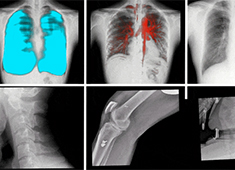

影響DR圖像質(zhì)量的因素有哪些方面

哪些因素會影響DR圖像質(zhì)量呢?普愛醫(yī)療歸納了以下幾大因素。當前國產(chǎn)DR都尤其重視圖像后處理系統(tǒng)的升級,如普愛醫(yī)療研發(fā)生產(chǎn)的多功能動態(tài)DR(型號:PLX8100),應用了公司自主研發(fā)的組織均衡技術(shù),它是基于低灰度區(qū)擴展到高...

百微米DR的臨床優(yōu)勢:呈現(xiàn)更豐富的成像細節(jié)

目前市面上已經(jīng)開始漸漸流行“百微米DR”,百微米DR好在哪里,具有什么樣的臨床優(yōu)勢?以PERLOVE品牌的PLX8100為例,這是一款大尺寸的多功能動態(tài)DR機,搭載了高性能的百微米平板,4K*4K采集矩陣與100μm像素...